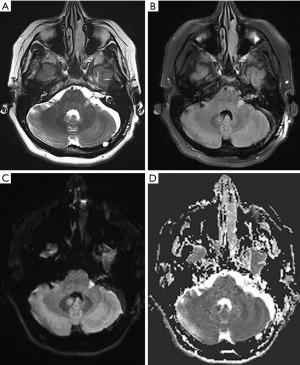

On examination, she was neurologically intact with a Glasgow Coma Scale (GCS) of 15. Unterberger’s test was negative. Preoperative pure tone audiometry showed normal hearing and speech discrimination in both ears with type A tympanograms consistent with normal middle ear function. Computed tomography (CT) of the brain demonstrated no significant widening of the left internal acoustic meatus compared to the contralateral side (Figure 1). CT angiography and magnetic resonance imaging (MRI) also revealed a complex 20 mm × 9 mm × 7 mm nidus of blood vessels in the left intracanalicular portion of the internal acoustic meatus extending into the cerebellopontine angle (Figure 1). There was a meatal loop arising from the anterior inferior cerebellar artery (AICA).

Post-operative cerebral angiography demonstrated successful complete obliteration of the AVM (Figure 3). Diffusion-weight imaging sequence revealed a small acute infarct of the left middle cerebellar peduncle likely related to endovascular embolization (Figure 4). On 3-month follow-up, she had persistent left sided sensorineural hearing loss but an improving House-Brackmann 3 palsy. She was reviewed by speech pathology both as an inpatient and outpatient given her hearing loss.